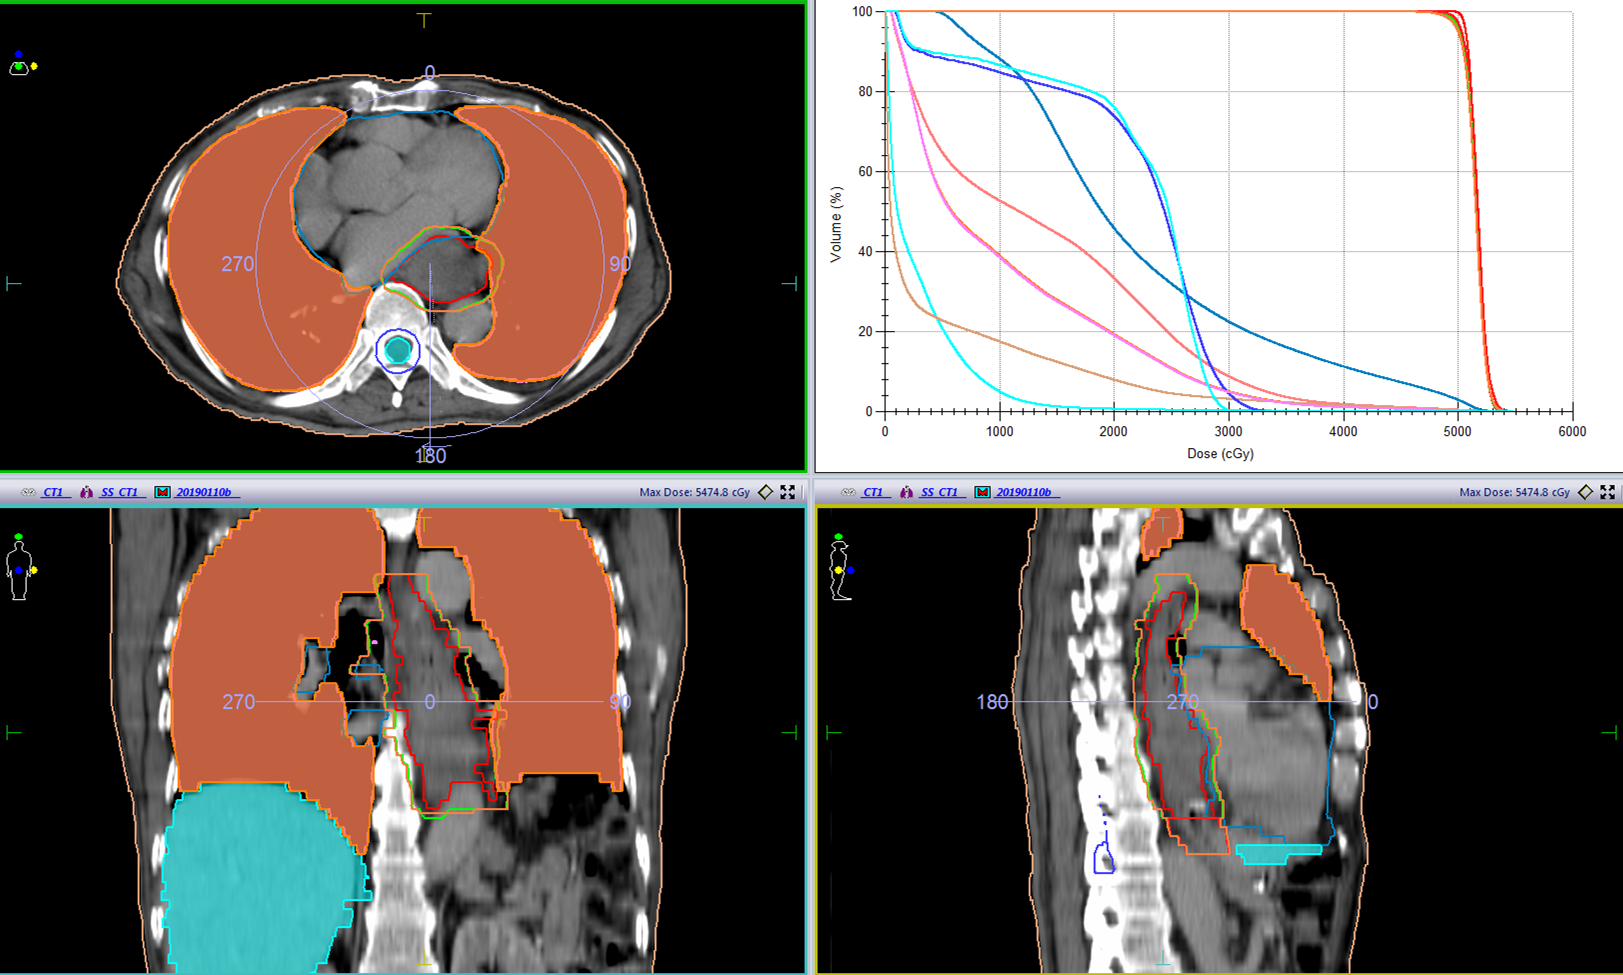

(1)2019-01-08进食梗咽症状加重入院,2019-01-14–02-22开始食管及吻合口放疗,以定位CT所示食管肿瘤为GTV,GTV及其上方75px食管外放12.5px为PTV, 95%PTV=5600cGy/28f,吻合口向下50px小肠外放12.5px为PTV1,95%PTV1=5000cGy/25f

(2)2019-04-08–05-15开始腹腔肿大淋巴结放疗,以定位CT所示腹腔淋巴结为GTV,GTV外放12.5px为PTV,95%PTV=5040cGy/28f